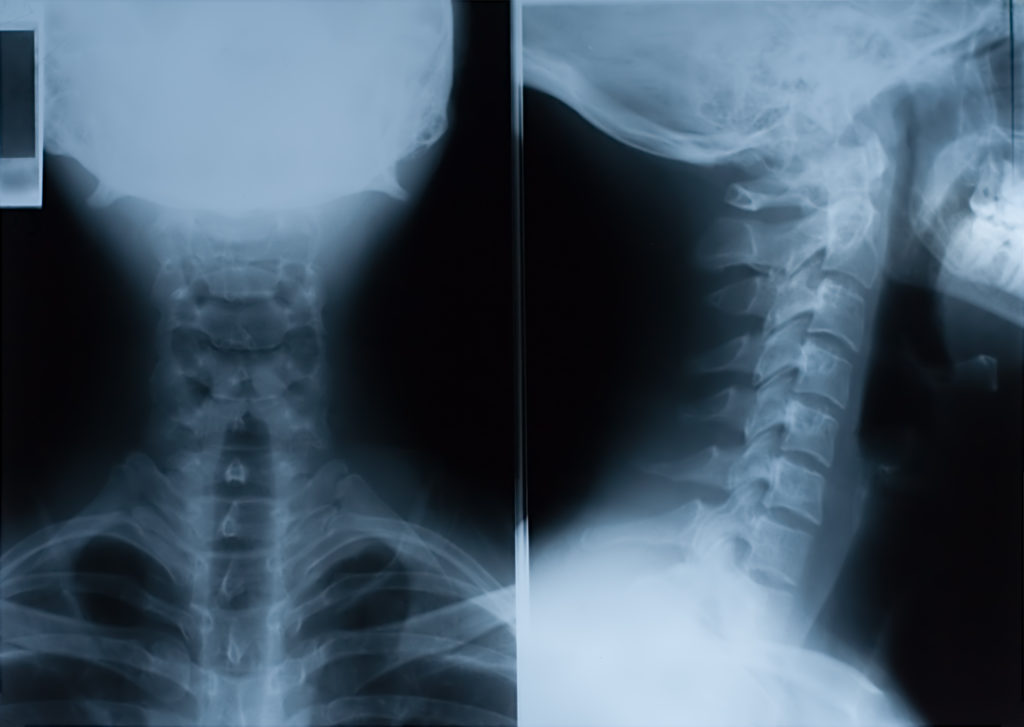

Human cervical spine xray, neck radiography Stock Photo Alamy Head And Neck Cancer X Ray These may include ct scans, pet scans, mris, or a panorex. Oral, oropharyngeal, laryngeal, and hypopharyngeal lesions are. In this work, we present an overview of main modalities of imaging and principles of their application especially in head and neck. Head and neck cancer treatment often involves surgery to remove the cancer. Other treatments might include radiation. Cancers that are. Head And Neck Cancer X Ray.